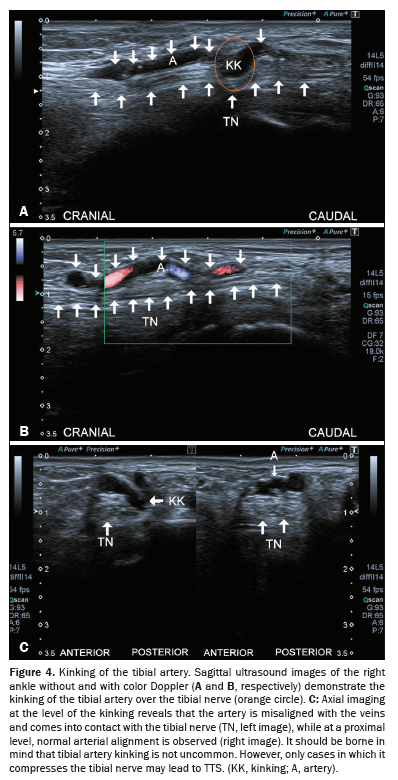

Vascular malformations

Venous malformations such as Klippel-Trénaunay syndrome can also impinge on the tibial nerve in the tarsal tunnel, leading to TTS(8), as depicted in Figure 5.